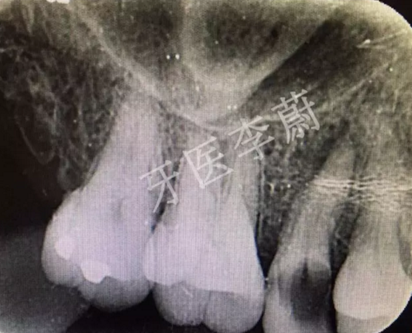

局部X牙片

X片示:15殘冠影,根尖有骨密度降低影。

口腔檢查:15冠部齲損,探及大量腐質(zhì),舌側(cè)冠折至齦下約2mm,近、遠(yuǎn)中壁亦部分齲壞,松動(dòng)Ⅰ°,叩痛(-) ,牙齦無(wú)瘺管,舌側(cè)及近中被齦組織覆蓋。